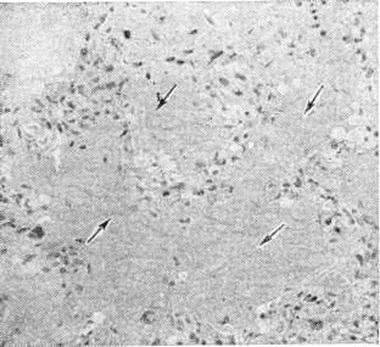

Тканевый парапротеиноз выражается в скоплении белковых масс в просветах сосудов, белковом пропитывании их стенок и стромы органов, отложении амилоида (параамилоида) и изредка кристаллических веществ. Белковые, амилоидоподобные отложения оксифильны, окрашиваются положительно при ШИК-реакции, в отличие от амилоида не обладают анизотропией. В почках, особенно при длительной протеинурии Бенс-Джонса (смотри полный свод знаний Бенс-Джонса белок), развивается картина парапротеинемического нефроза. Характерны обилие белковых цилиндров в канальцах (рисунок 5), дистрофия эпителия, его гибель и десквамация, очаговый нефрогидроз, отёк, возможна плазмоклеточная инфильтрация стромы. Цилиндры могут быть окружены гигантскими клетками, пропитаны солями кальция. Изменения клубочков незначительны. Имеется утолщение базальной мембраны, отложение белковых веществ в мезангии, иногда гиперплазия его клеток; дистрофия подоцитов с отложением в их цитоплазме белковых гранул. Часто наблюдается нефросклероз (смотри полный свод знаний). Для Миеломная болезнь типичен белковый отёк ткани лёгких (рисунок 6), стромы миокарда. Амилоид (параамилоид) при Миеломная болезнь отличается от других его разновидностей высоким содержанием в белковом компоненте низкомолекулярных фрагментов. Амилоид часто не даёт положительной реакции с красным конго, метахромазии с метиловым фиолетовым и толуидиновым синим; люминесцирует с тиофлавином Т и S, обладает анизотропными свойствами.